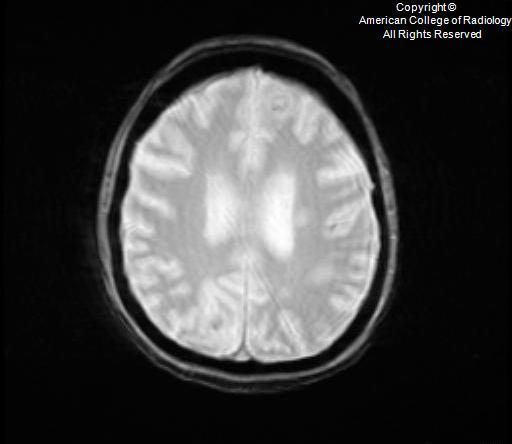

DDx of restricted diffusion on brain MR

A

• ischemia

• abscess

Configuration of cerebral lesiosn that demosntrate restricted diffusio

• rounded, diffuse restriction –> infectious etiology - abscess or septic emboli

• restriction only in the walls and projections of the lesion (not in its core)–> fungal abscesses

• special with fungal (esp with aspergillosis infection/abscess): T2-hypointense zones and magnetic susceptibility within the wall of cerebral Aspergillus lesions can be attributed to a dense population of Aspergillus paramagnetic hyphal elements, especially iron and magnesium, which are essential for hyphal growth. It has also been postulated that this MR finding may correspond to hemorrhage in the capsular wall.